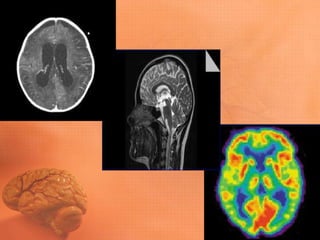

NEURORRADIOLOGIA • Até adécada de 70 do século passado os exames neurológicos de investigação eram: semiologia e exames complementares eletrofisiológicos e de imagem (ventriculografia, EEG e angiografia) extremamente grosseiros. • No início dos anos 70 é inventada, na Inglaterra, uma nova aplicação revolucionária para o Raio-x: a tomografia.

NEURORRADIOLOGIA • Pela primeiravez podíamos visualizar, de maneira direta e não invasiva, o conteúdo intracraniano. • Mas, a duração do exame era longa, mais de 5 minutos para um corte do encéfalo. • Com o desenvolvimento da informática e na aquisição de imagens, os exames hoje duram segundos.

NEURORRADIOLOGIA • No inícioda década de 80 outra revolução se procede: a Ressonância Magnética Nuclear. • Ela utiliza campos magnéticos, sem radiação ionizante e permite através de sofisticados programas de aquisição de imagens cortes anatômicos extremamente detalhados.

NEURORRADIOLOGIA • Além dosmétodos de imagem morfológicos, vamos ver o desenvolvimento dos métodos funcionais. • Permitem a localização anatômica e também das principais funções cerebrais. • PET SCAN • Neuronavegação – localização trans- operatória.